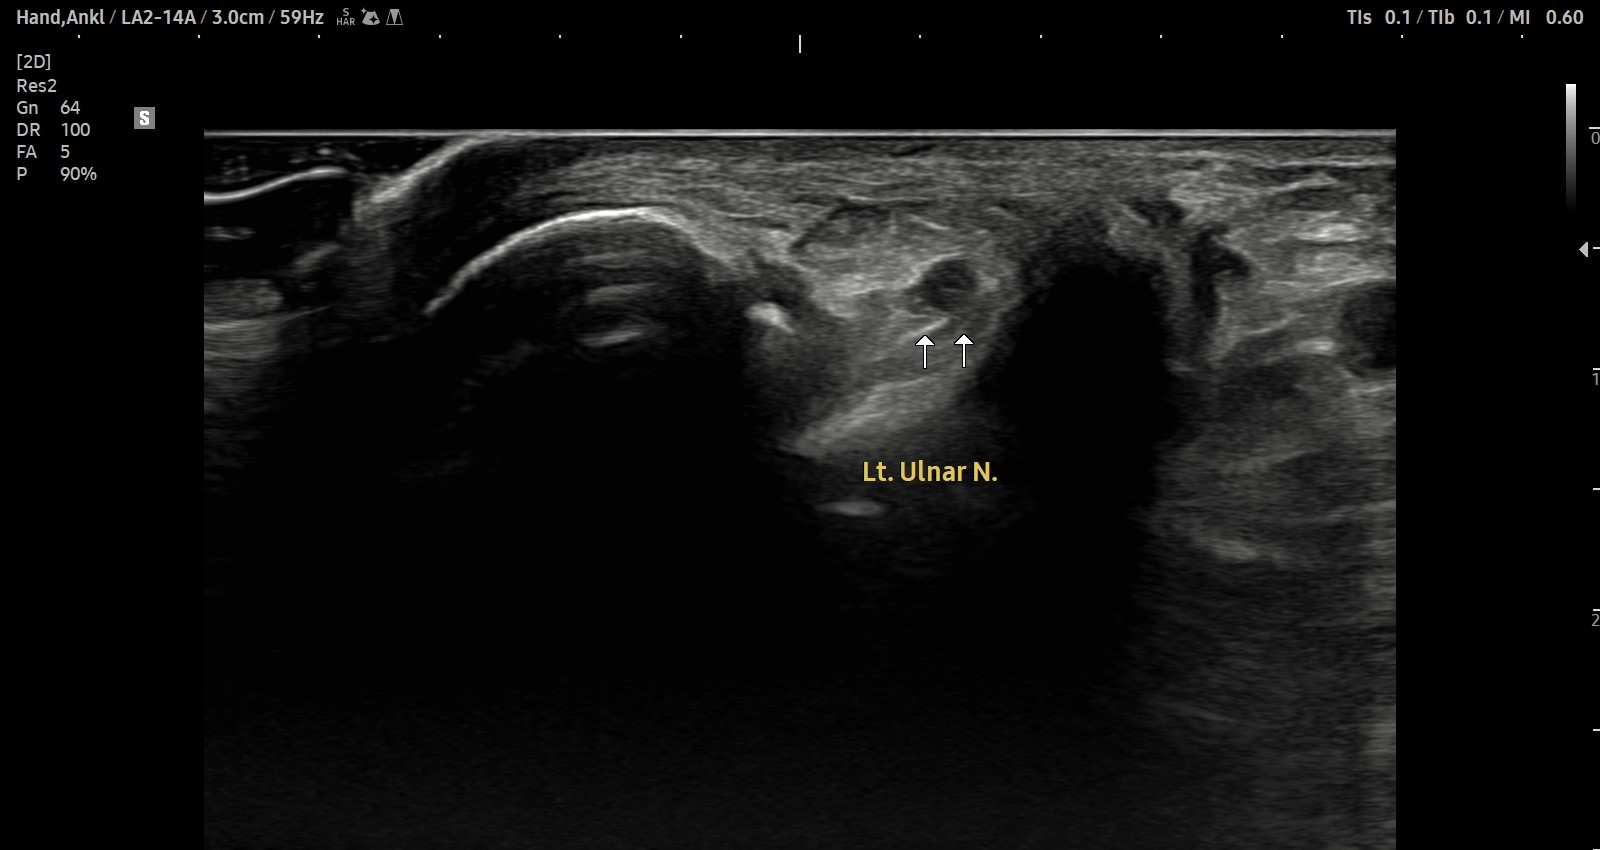

- 치료기간 : 25 . 9 . 27 ~ 25 . 11 . 19

- 치료횟수 : 12 회